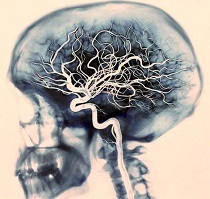

- Transcraniális. Ebben a vizsgálatban, a vérerek bekövetkezik diagnosztika, amelyek belül vannak koponyaüreg és közvetlenül táplálja az agy.